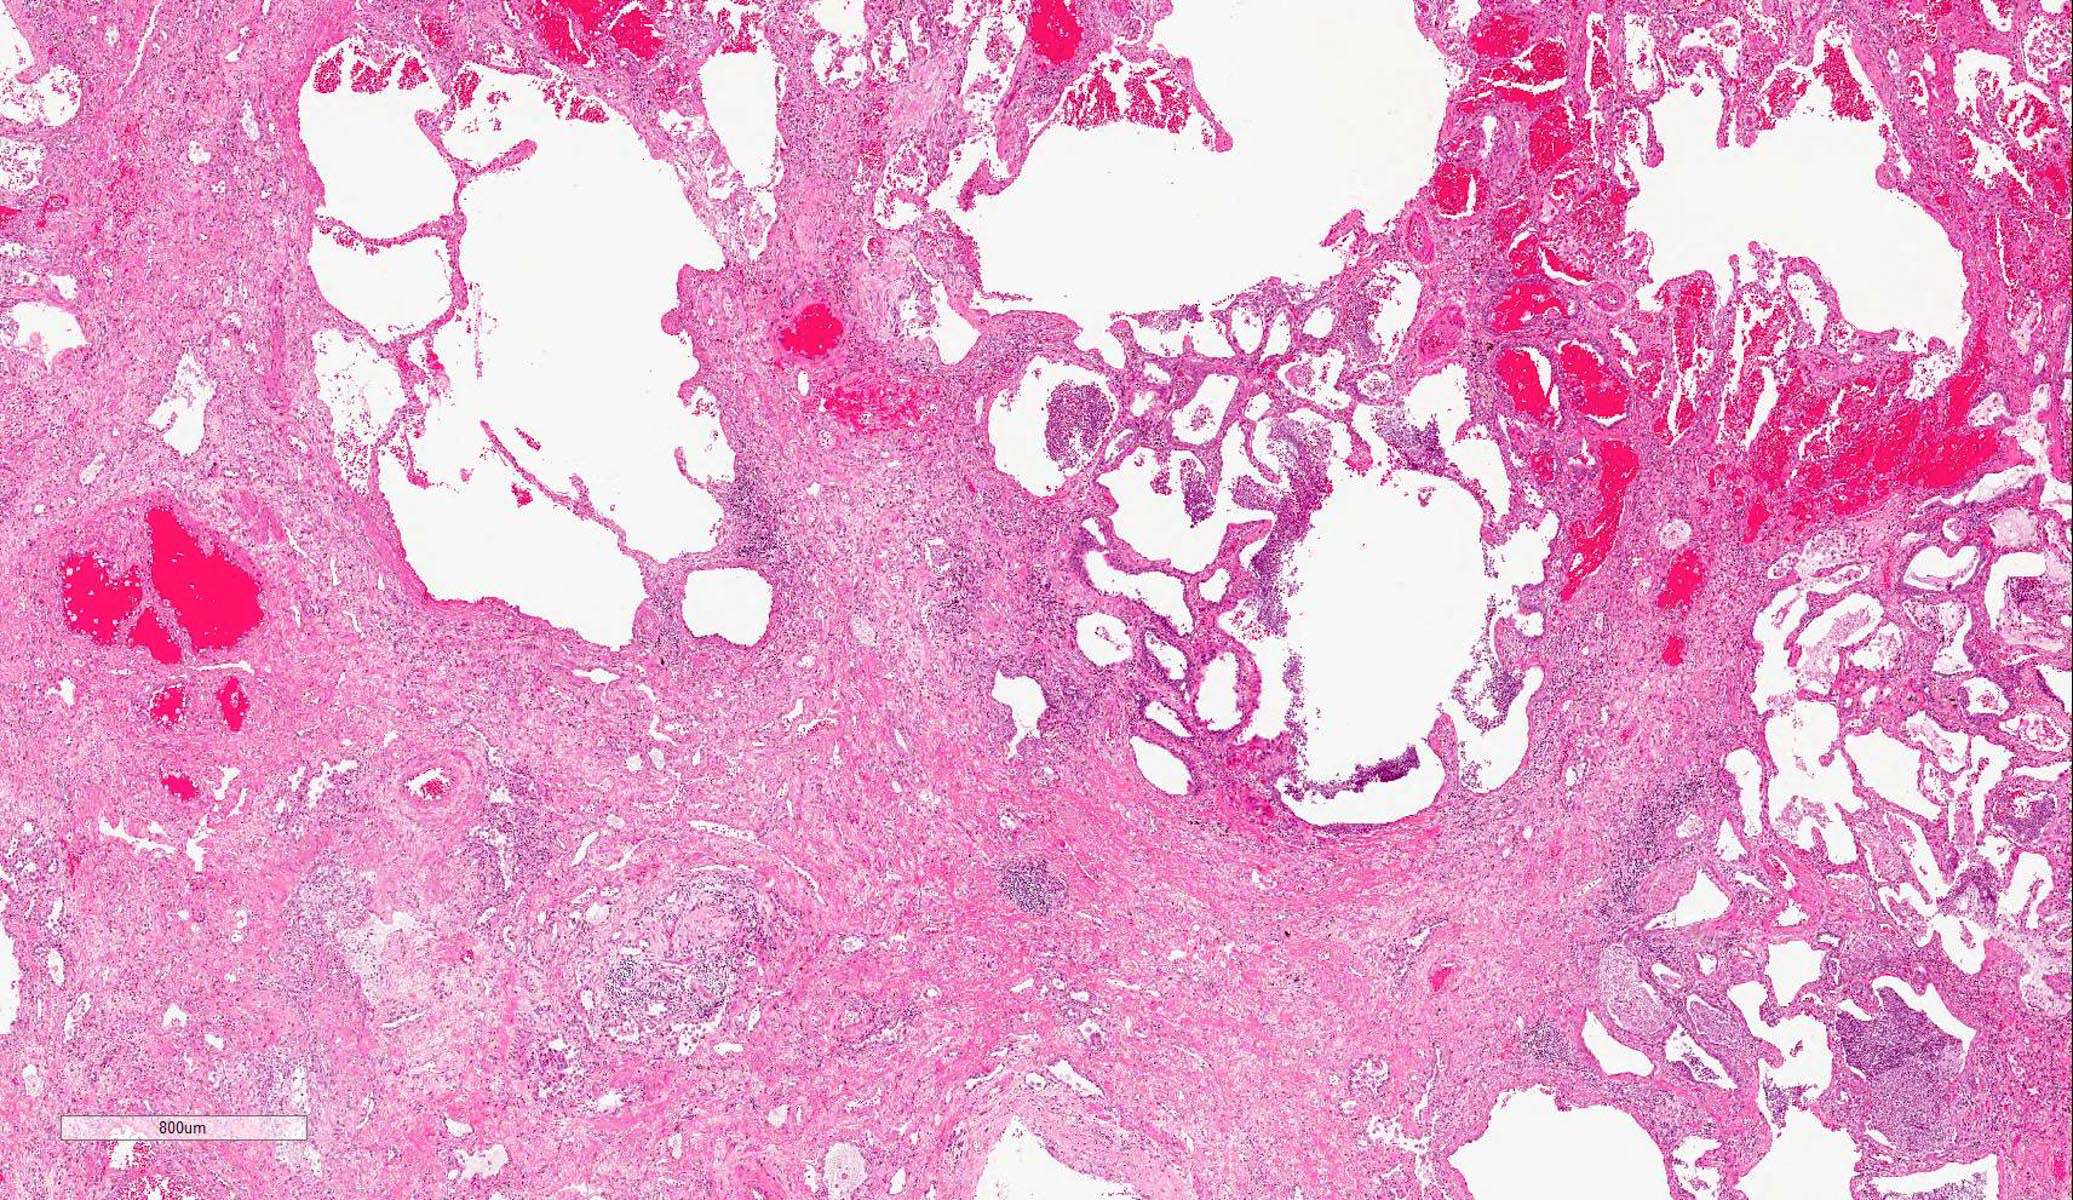

Microscopic (histologic) description

- Histopathology of DAD progresses from exudative (acute) phase through proliferative / organizing (subacute) phase to chronic fibrotic phase roughly corresponding to the period of ARDS (Am J Pathol 1976;85:209, Arch Pathol Lab Med 2010;134:719, Clin Chest Med 2000;21:435, N Engl J Med 2000;342:1334)

- Phase of the disease is almost synchronous throughout the lung

- Exudative (acute) phase

- Alveolar change

- Hyaline membranes on alveolar duct or sacs

- Interstitial and intra-alveolar edema

- Collapsed alveoli

- Proliferative / organizing (subacute) phase

- Alveolar change

- Remnants of hyaline membrane with or without organization

- Interstitial and intra-alveolar proliferation of myofibroblasts

- Fibrosis phase

- Alveolar change

- Collagenous fibrosis

- Microscopic honeycomb-like change

- Traction bronchiolectasis

Microscopic (histologic) images

Contributed by Akira Yoshikawa, M.D. and Yale Rosen, M.D.